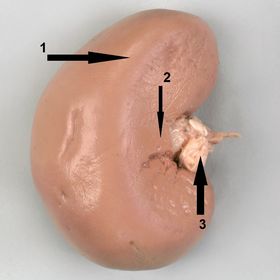

1) identify the side 2) mention structures related to 1 and 2 3) identify 3 1) right kidney 2) 1- liver (right lobe) 2- 2nd part of dudenum 3) renal vein ( most anterior in position)